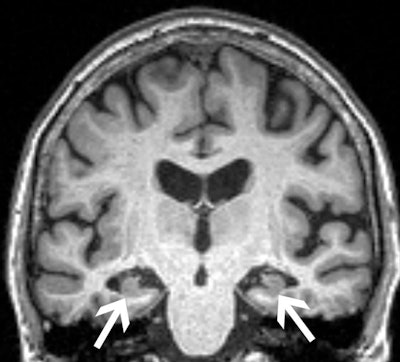

A brain MRI in patient with mild cognitive impairment. Image courtesy of Joshua Wibecan, MD.

According to the findings, only 50.9% of Black patients underwent MRI testing for cognitive impairment, compared with 60% of white patients, 67% of Hispanics, and 68.2% in the Other group. In addition, the average age at imaging for cognitive impairment among Black patients was 72.5 years, compared with 67.8 years for white patients, 66.5 years for Hispanics, and 66.7 years for the Other group.

“Our study demonstrates two main findings. First, Black patients who received MRI or CT for cognitive impairment were significantly older than patients from other races. Second, Black patients were significantly less likely to be imaged with MRI, the optimal type of imaging for cognitive impairment, as opposed to CT,” Wibecan said.